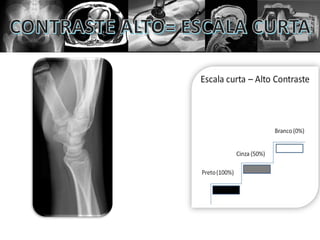

• CONTRASTE ALTO = ESCALA CURTA

MAIS CONTRASTE

CONTRASTE

IMAGEM

PADRÃO

MENOS

NITIDEZ

MAIS

PERDE

DETALHES

Contraste alto ou baixo não significam ser bom

ou ruim por si só. Diferentes estruturas precisam

de determinado tipo de contraste específico.